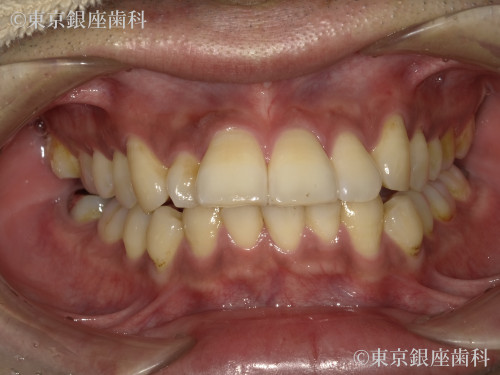

After

インビザライン:ライトパッケージ

側方前突